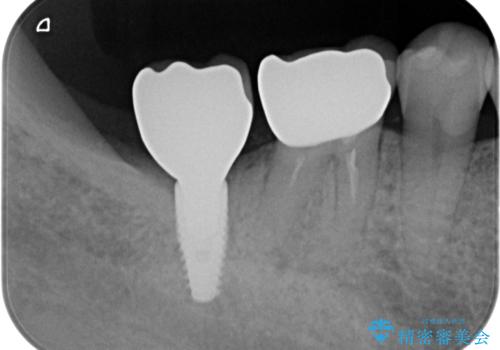

- 失った右下最後方臼歯の咬合機能の回復を求めてインプラント治療を希望され来院されました。

インプラントを埋入するのに十分な骨の量がCT検査により確認されたので、インプラントによる治療を計画します。

- 44万円(インプラント・ジルコニアカスタムアバットメント・ジルコニアクラウン・仮歯)費用は治療当時の料金となります

第二大臼歯は失ってしまうと咀嚼効率が10-30%程度低下してしまうと言われている、食事で物を噛み切るのに非常に重要な歯です。

失ってしまった奥歯をインプラントを用いて咬合機能回復することで、残っている他の歯を守ることにもなります。